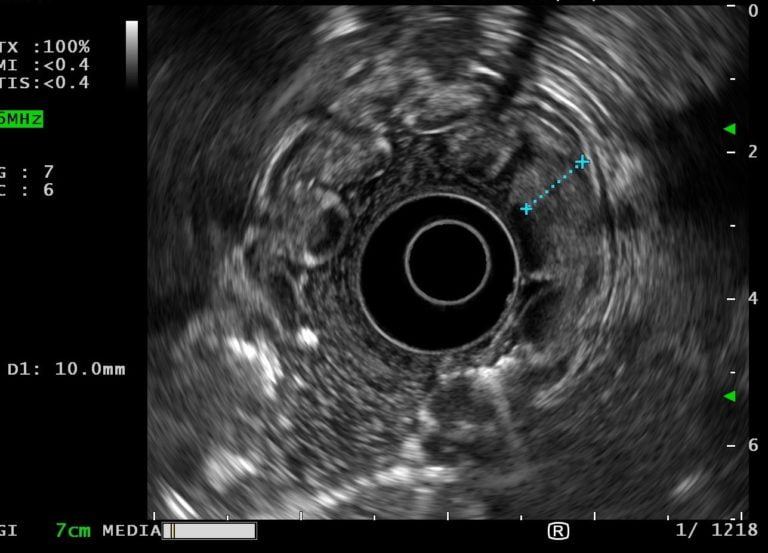

Tissue specimens of altered gastric mucosa were obtained using standard biopsy forceps. Endoscopic ultrasound showed thickening of the mucosal layer of the stomach body with preservation of wall stratification. Antrum wall had normal thickness and structure (Fig. 2 and Video 1).

Figure 2. EUS showing a gastric wall with 10 mm with an echogenic thickening of the mucosal layer wall with preservation of normal architecture.